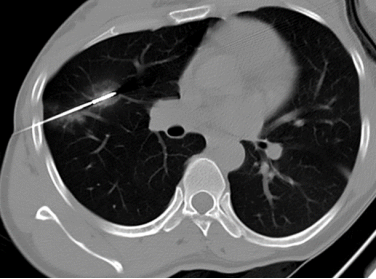

术中精准穿刺,微波消融毁损病灶

经过周密的术前准备,王女士在局部麻醉下接受了微波消融术。

术中医生先按照术前既定的穿刺路线通过麻醉针进行定位,然后引入微波消融针精准穿刺到磨玻璃结节病灶,消融3分钟后可见原磨玻璃结节完全被椭圆形热消融带所包裹,提示手术成功,病灶被“热损毁”。

图片

术中穿刺针精准穿刺磨玻璃结节病灶